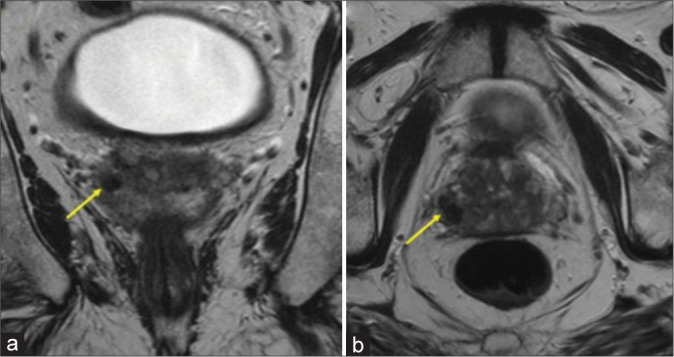

Idiopathic granulomatous mastitis is a rare, chronic inflammatory disease of the breast of uncertain etiology that can mimic breast cancer. In rare instances, it may emerge secondary to trauma to the breast. We present a case of a 66-year-old woman who initially underwent a benign stereotactic core-needle biopsy of her left breast complicated by a small hematoma which initially remained unchanged mammographically and sonographically for 1 year; then, it enlarged unexpectedly at the 21-month interval follow-up prompting an ultrasound-guided biopsy revealing granulomatous mastitis.

Abstract Image